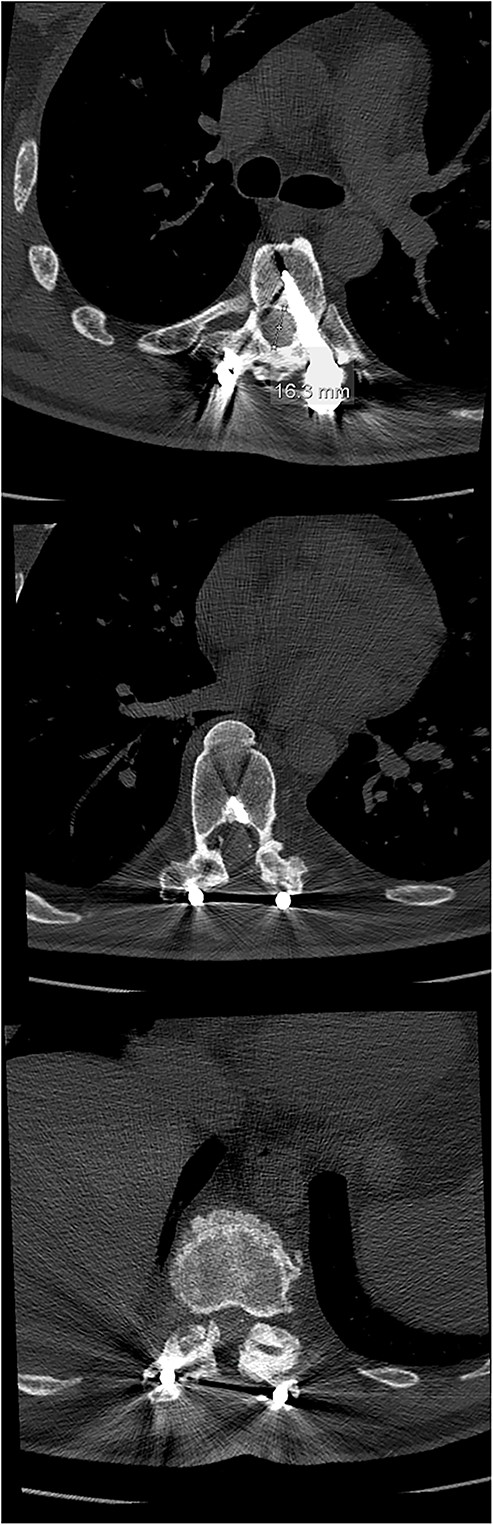

Six weeks after surgery he was transferred to a tertiary rehabilitation center, ambulating using a walker, but remained wheelchair-bound for longer distances. The postoperative pain was manageable with non-opioids. During the regular follow-ups, the paraplegia with severe spasticity persisted, without significant pain. A subsequent insertion of the intrathecal baclofen pump in a tertiary rehabilitation facility enabled the patient to manage the muscle spasms in his lower limbs, particularly during transfers from the wheelchair to bed and vice versa. The patient was able to urinate spontaneously with minimal urine retention, and no need for self-catheterisation, reporting satisfaction with the outcome of the surgery and rehabilitation, which enabled him a return to his workplace and retain a significant level of independence in everyday activities. On the final follow-up imaging, 4 years after the surgery, no significant deformity progression and no evidence of neurologic impairment were observed (Figs 4 and 5).

Final follow-up CT scan (axial views), showing adequate width of the spinal canal at Th6 (above), Th9 (middle) and Th11 (below).